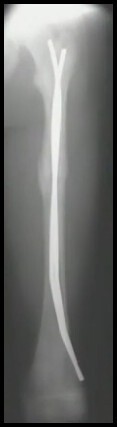

9

Q

FX Diafisária do Fêmur

Detalhe Haste Flexível (2)

A

1. Ideal < 50 Kg e Padrões Estáveis de FX

2. Duas Hastes diâmetro 40% do diâmetro do ISTMO (80% do canal)